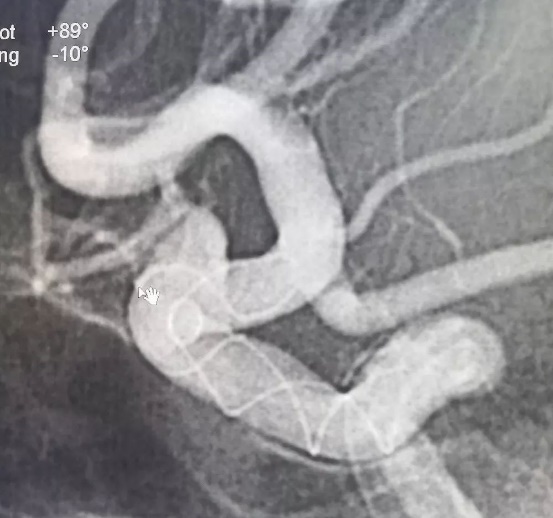

Tubridge®血管重建装置专用支架导管T-track到位,引入4.0mm*30mm支架。

准确定位后,锚定支架头端,缓慢推送支架的同时控制支架张力,顺利释放支架。

为进一步确保Tubridge®血管重建装置完美贴壁,上J型导丝支架内“按摩”。

多角度确认支架已完全贴壁。

正侧位造影示动脉瘤内造影剂明显滞留,载瘤动脉通畅,血流导向作用显著。